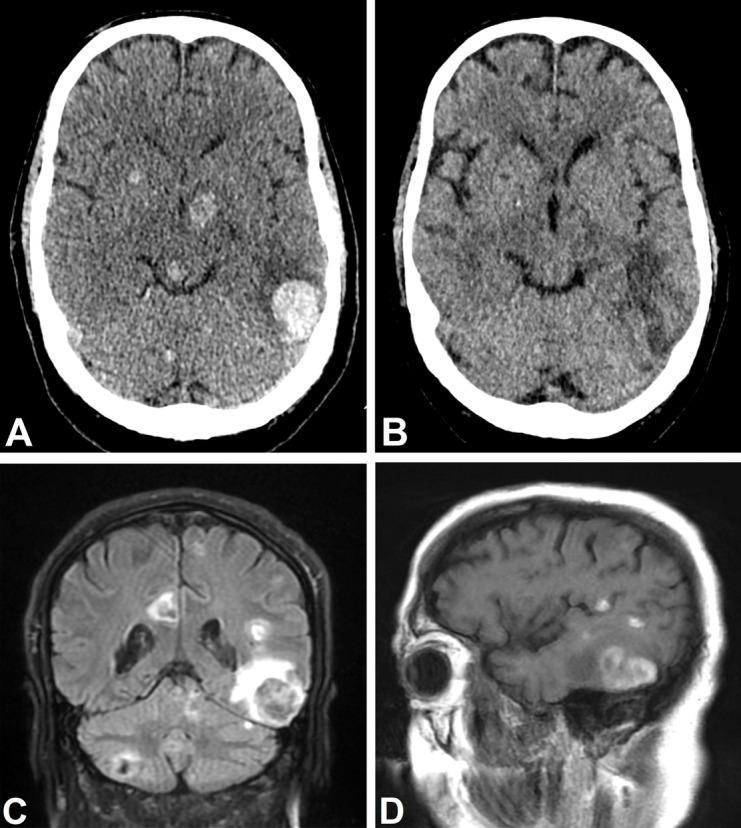

The present case contributes to the limited literature on central nervous system involvement of blastic plasmacytoid dendritic cell neoplasm (BPDCN).  CASE PRESENTATION : A 63-year-old male presented to the department of neurology with a three-day history of rapidly progressing headache, fatigue, and confusion. Physical examination revealed multiple bruise-like skin lesions. Initial laboratory workup raised suspicion of acute leukemia, and a brain computer tomography identified several hyperdense processes. A bone marrow biopsy gave the diagnosis BPDCN, a rare and aggressive hematologic malignancy derived from plasmacytoid dendritic cells with a poor prognosis. Lumbar puncture showed not only signs of BPDCN, but also cerebral toxoplasmosis, thus providing a differential diagnosis. Despite intensive systemic and intrathecal chemotherapy, the patient died 25 days later due to multi-organ failure.

一名 63 岁男性因头痛、乏力和意识模糊 3 天就诊于神经内科。体格检查发现多处类似瘀斑的皮肤损伤。初始实验室检查提示急性白血病,颅脑计算机断层扫描(CT)发现多个高密度病变。骨髓活检诊断为 BPDCN,这是一种罕见的侵袭性血液系统恶性肿瘤,起源于浆细胞样树突细胞,预后不良。腰椎穿刺不仅提示 BPDCN,还提示脑弓形虫病,从而提供了鉴别诊断。尽管进行了强化全身和鞘内化疗,患者仍因多器官功能衰竭于 25 天后死亡。